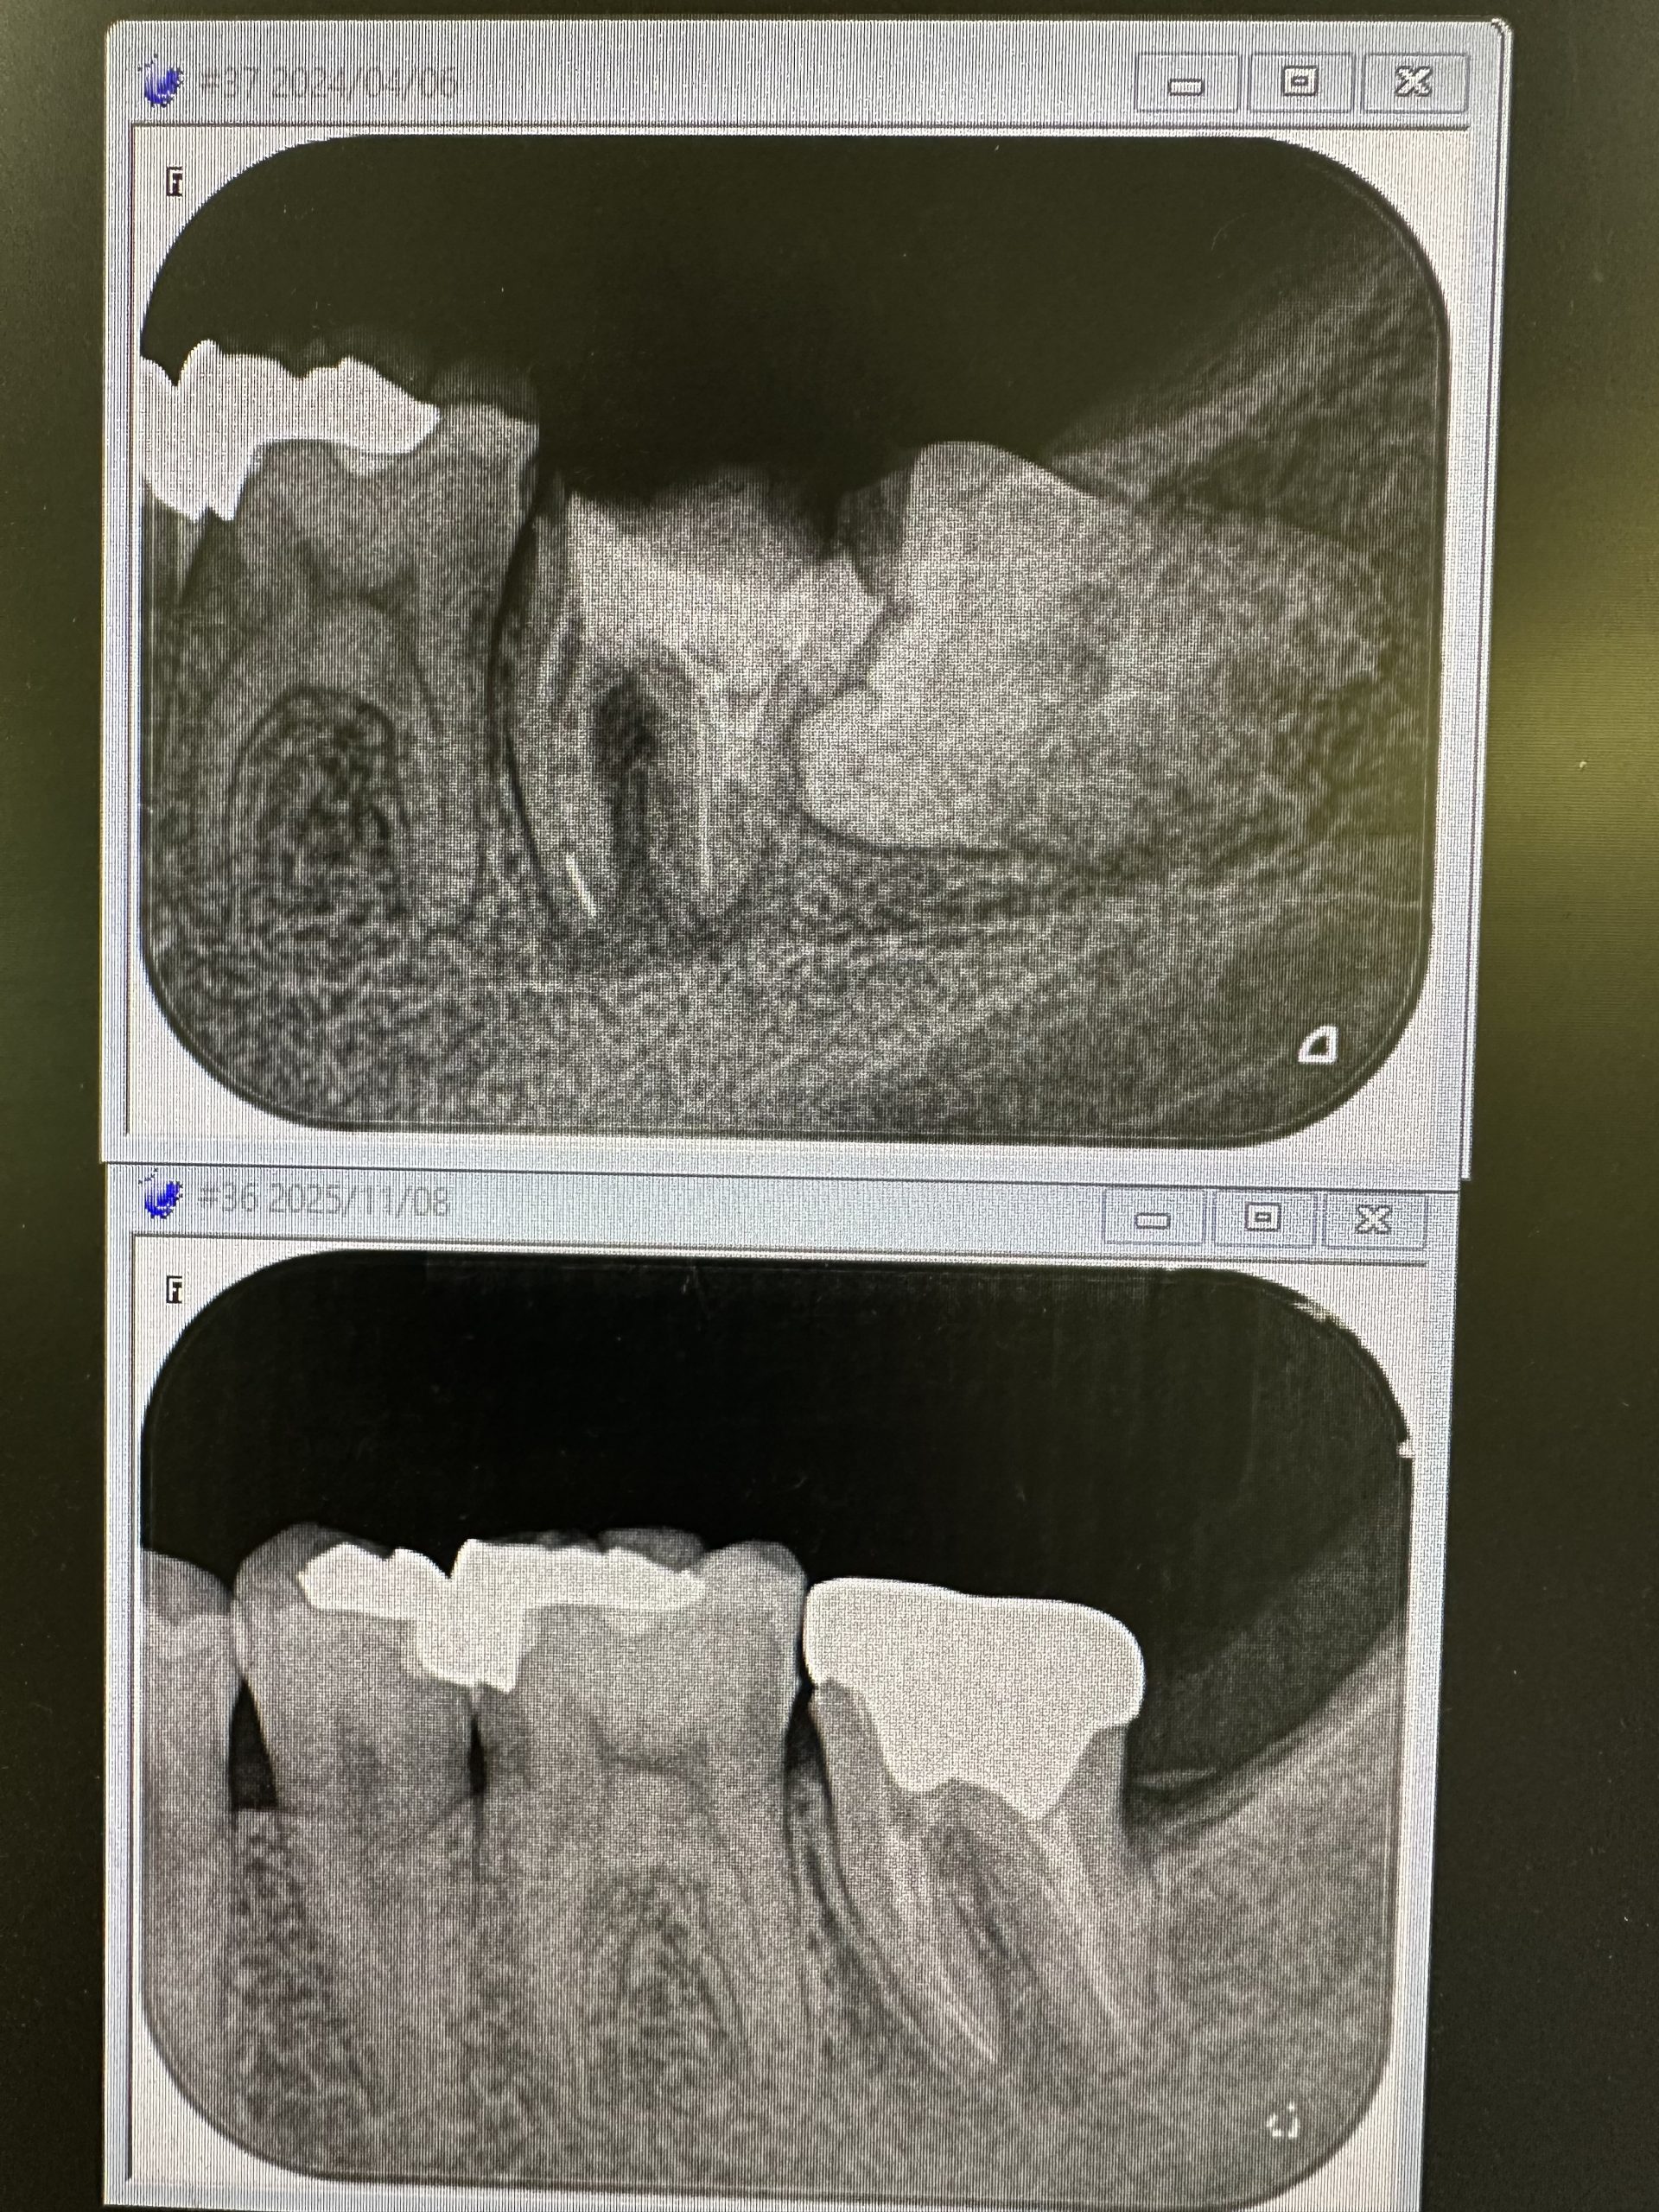

非常に稀だが、根管治療終盤、根充直前でキャンセルする方がいる。折角病巣が縮小してきたのに‥

銀歯にしたくないが為に!🤪

本医院では、保険治療でさえ純度100%のガッタパーチャー使用、術式殺菌レベルが違うのにね🤪